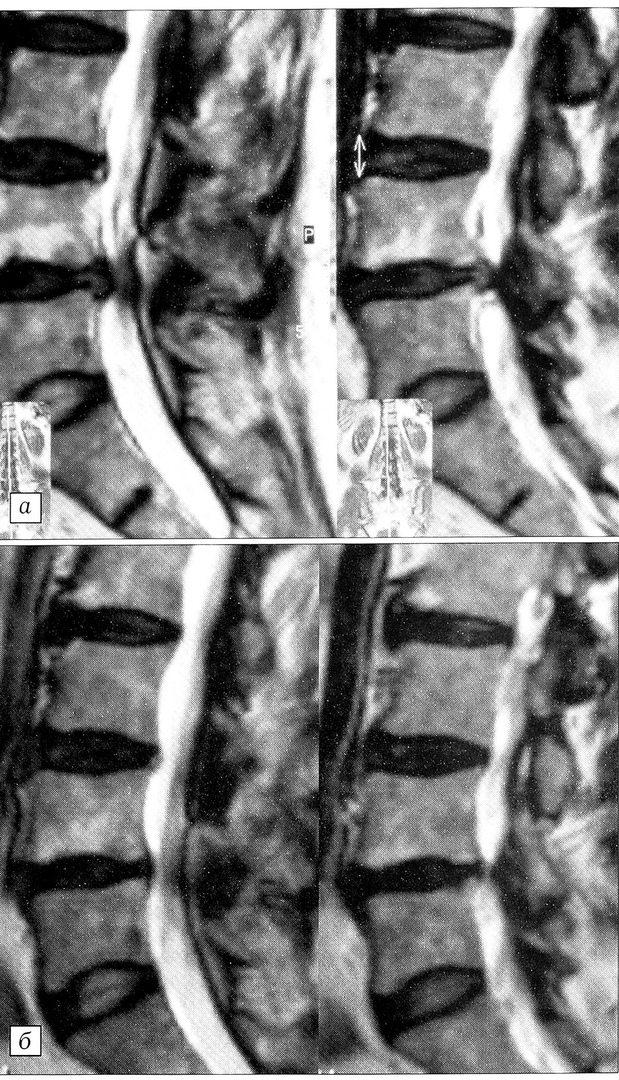

Рис. 2. МРТ поясничного отдела позвоночника больного И. в сагиттальной проекции: a — до операции, б — после операции.

Больной И.,32 лет, обратился в поликлинику 3.01.00 с жалобами на боль в поясничной области. Произведена рентгенография поясничного отдела позвоночника с функциональными пробами, поставлен диагноз: дискоз L5-S1, правосторонний компрессионно-корешковый (S1) синдром (болевой аудит 38 баллов). Назначена консервативная терапия острой фазы. Спустя 2 нед выраженного улучшения не наступило (болевой аудит 42 балла), и больной был госпитализирован. В отделении неврологии продолжена интенсивная терапия, однако эффект лечения через 10 дней был признан неудовлетворительным (болевой аудит 54 балла). Проведена МРТ поясничного отдела позвоночника — выявлен правосторонний парацентральный пролапс диска L5-S1 с признаками секвестрации и невральной компрессией (рис. 2, а).

27.01.00 выполнена операция — микродискэктомия L5-S1 справа с удалением секвестра. Через сутки после операции (болевой аудит 16 баллов) пациенту разрешено ходить в ортопедическом поясе. Через месяц боли в позвоночнике и нижних конечностях не беспокоят (болевой аудит 6 баллов), на контрольной МРТ признаков компрессии невральных структур в зоне операции не выявлено (рис. 2, б). По данным функционального тестирования (мониторинг движений в поясничном отделе позвоночника), показатели амплитуды, скорости и ускорения в поясничном отделе соответствуют норме. Пациенту разрешено приступить к работе по облегченному графику.

Таким образом, больной вернулся к труду через 2 мес с момента первого обращения к врачу (2 нед в поликлинике, 2 нед в стационаре неврологического профиля, 1 мес восстановительного лечения после операции).